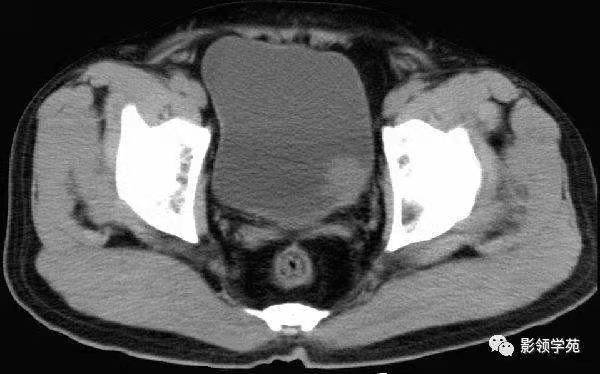

是的,CT是这样的↓

b膀胱镜为什么消毒泌尿外科迈向微创时代新“镜”界——膀胱镜_https://www.jmylbn.com_新闻资讯_第7张

CT也能看到结节,还能看到膀胱周围组织的情况,但是还是不能确定结节的性质。